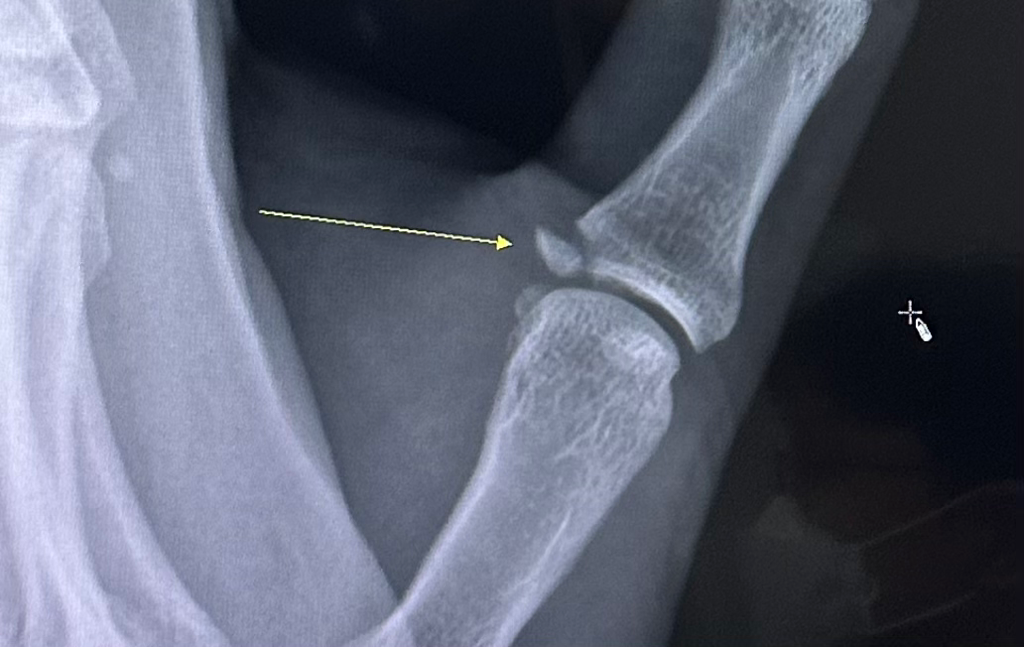

왼손 엄지 근위지골 골절 수술 필요할까요?

집근처 큰 정형외과 병원에서 mri 랑 cr 찍어봣는데

골절돼 떨어진 골편에 인대는 붙어 있다고 설명들었습니다.

진료보신 선생님이 골편 정복이 필요해보여서 수술필요해 보이고 수술한다면

열어서 제 위치에 가장 얇은 핀으로 고정 해 5-6주간 핀 갖고 있게끔 한다고 합니다.

1. 건열 골절로 의심되며 수술적 치료가 필요하다 생각됩니다.

2. 수술이 너무 늦어지면 수술이 어려워지게됩니다.